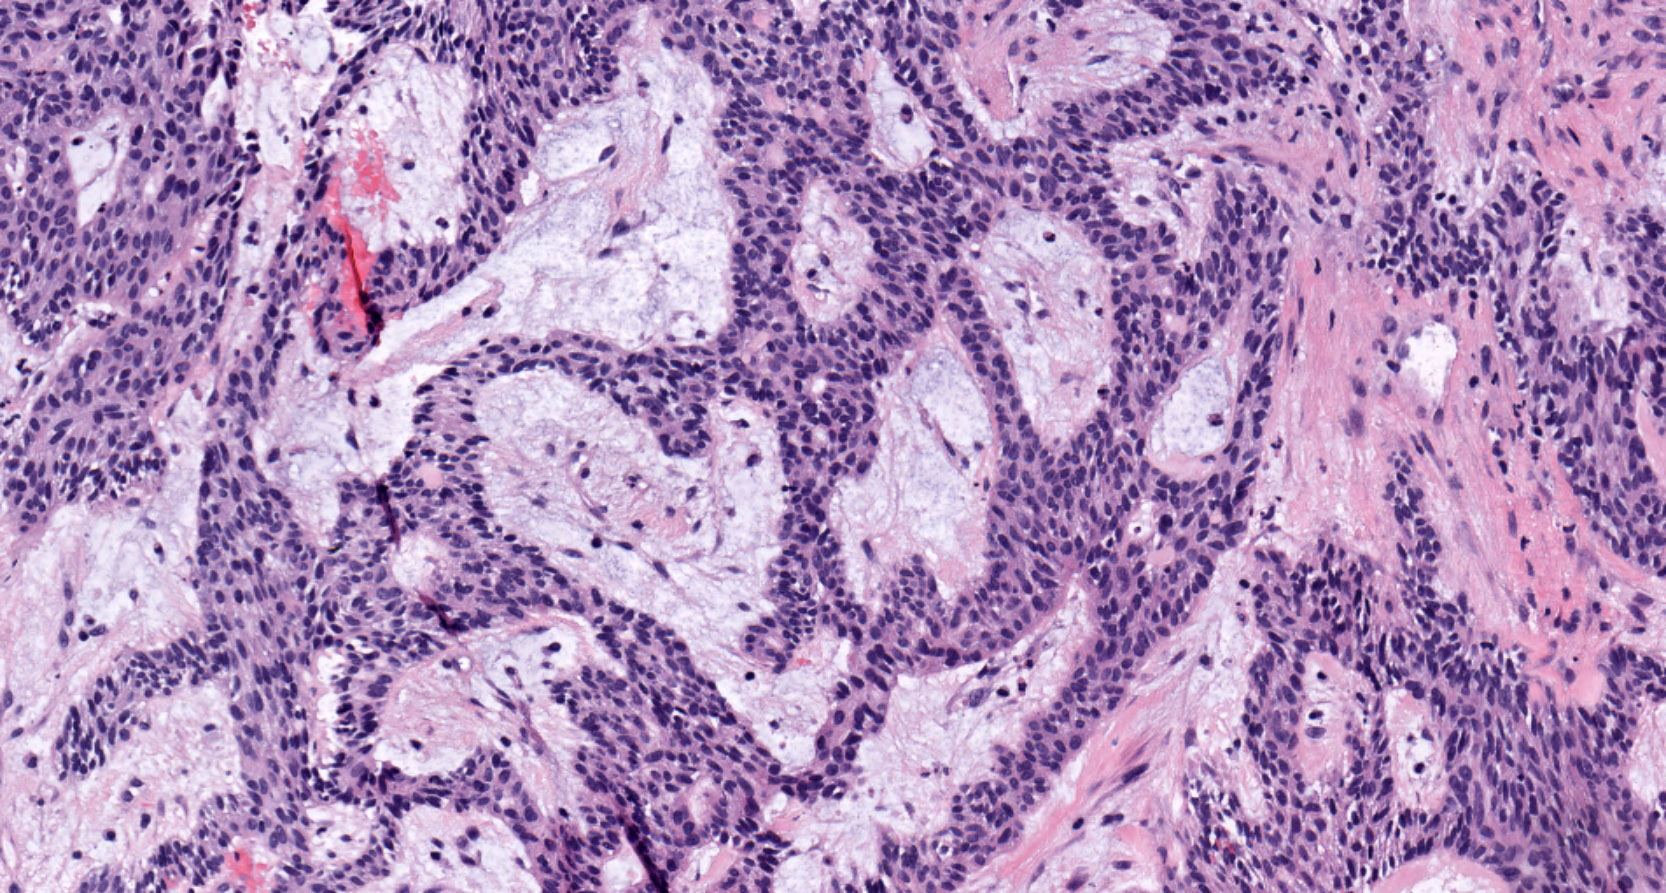

Microscopic (histologic) description

- Within the epithelial islands and cords of conventional ameloblastoma and the cystic epithelial lining of unicystic ameloblastoma, the odontogenic epithelium shows similar changes:

- Columnar cells with hyperchromatic nuclei at basal layer, exhibiting peripheral palisading

- Cells show reverse polarization away from basement membrane (Vickers-Gorlin change)

- Subnuclear vacuolization

- Suprabasal cells with a loose, network-like arrangement, recapitulating stellate reticulum formation seen in normal odontogenesis

- Ameloblastoma, conventional type has at least 6 histopathological patterns

- Single patterns may predominate within a given lesion, often mixed with 1 or more patterns

- Microscopic pattern has no documented prognostic significance

- Desmoplastic: compressed and angular islands of epithelial tumor cells with dense moderately cellular fibrous connective tissue or collagenous stroma; the formation of metaplastic bone trabeculae is also described

Microscopic (histologic) images

Contributed by Kelly Magliocca, D.D.S., M.P.H. and Anne C. McLean-Holden, D.M.D., M.S.